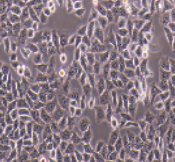

HCCLM3

高转移肝癌细胞

上皮样

HCCLM3 人高转移肝癌细胞

肝癌;男性